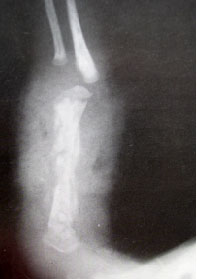

除了一般的理學檢查以外,有時因病情需要必須做一些檢驗,例如:驗血’照X-光若醫師懷疑骨髓炎的可能,會建議住院做進一步檢查與治療,有時因初始症狀輕微,而所有檢驗也在正常的範圍內,但醫師基於經驗及專業判斷,強烈懷疑骨髓炎時,也會給予注射抗生素,以免因不明顯的潛伏期(事實上細菌一直不停的繁殖,持續破壞骨骼,只是外表看不出來罷了)而空做等待,使病情更為惡化;因為等x-光出現骨骼破壞變化時往往已經太遲,很多家長不了解這種情形,往往會懷疑醫師的醫術,小則要求轉院,大則興師問罪,委實替有心之醫療人員澆了一盆冷水,甚至因此採取消極保守的治療方式,不但造成醫病關係的緊張,也易使病情更進一步惡化,實在得不償失!其實這也是嬰幼兒骨髓炎既特別又令人莫可奈何之處!